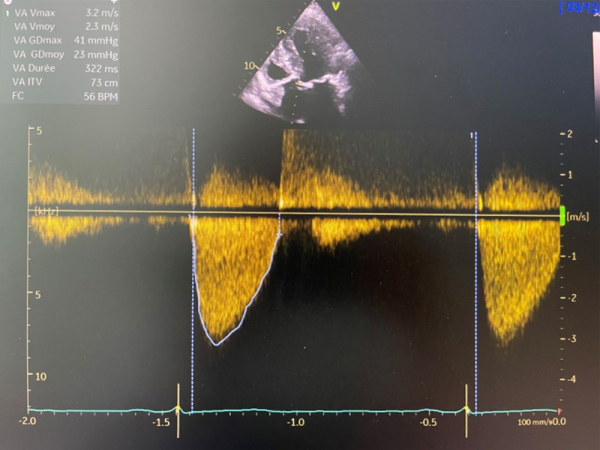

Paramètres échographiques

Figure 1

Figure 2

Figure 3

Figure 4

Figure 5

Figure 6

- Maladie aortique sur valve tricuspide avec RAC serré (V max 4,1 m/s, gradient moyen 41 mmHg, IP 0,27, surface 0,95 cm²) et IA modérée (grade 2)